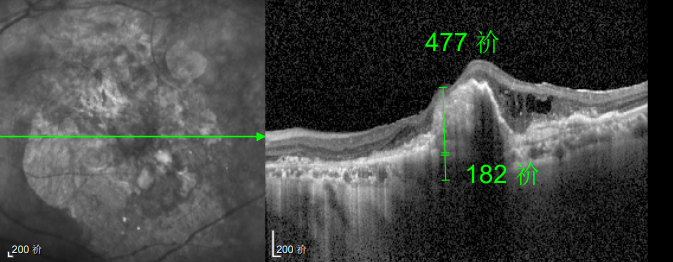

△规划化治疗后的左眼

幸运的是,三年后的一次例行复查中,医生通过眼底监测及时发现林婆婆的右眼眼底病变问题,确诊为湿性老年性黄斑变性。得益于定期筛查的及时性,王晓波主任第一时间为她启动治疗,最终成功将右眼矫正视力稳定在0.8左右。

如今,林婆婆依然坚持每半年进行一次巩固治疗,谈及右眼的好视力,她感慨道:“全靠听话遵医嘱,不然现在可能早就看不清东西了。”